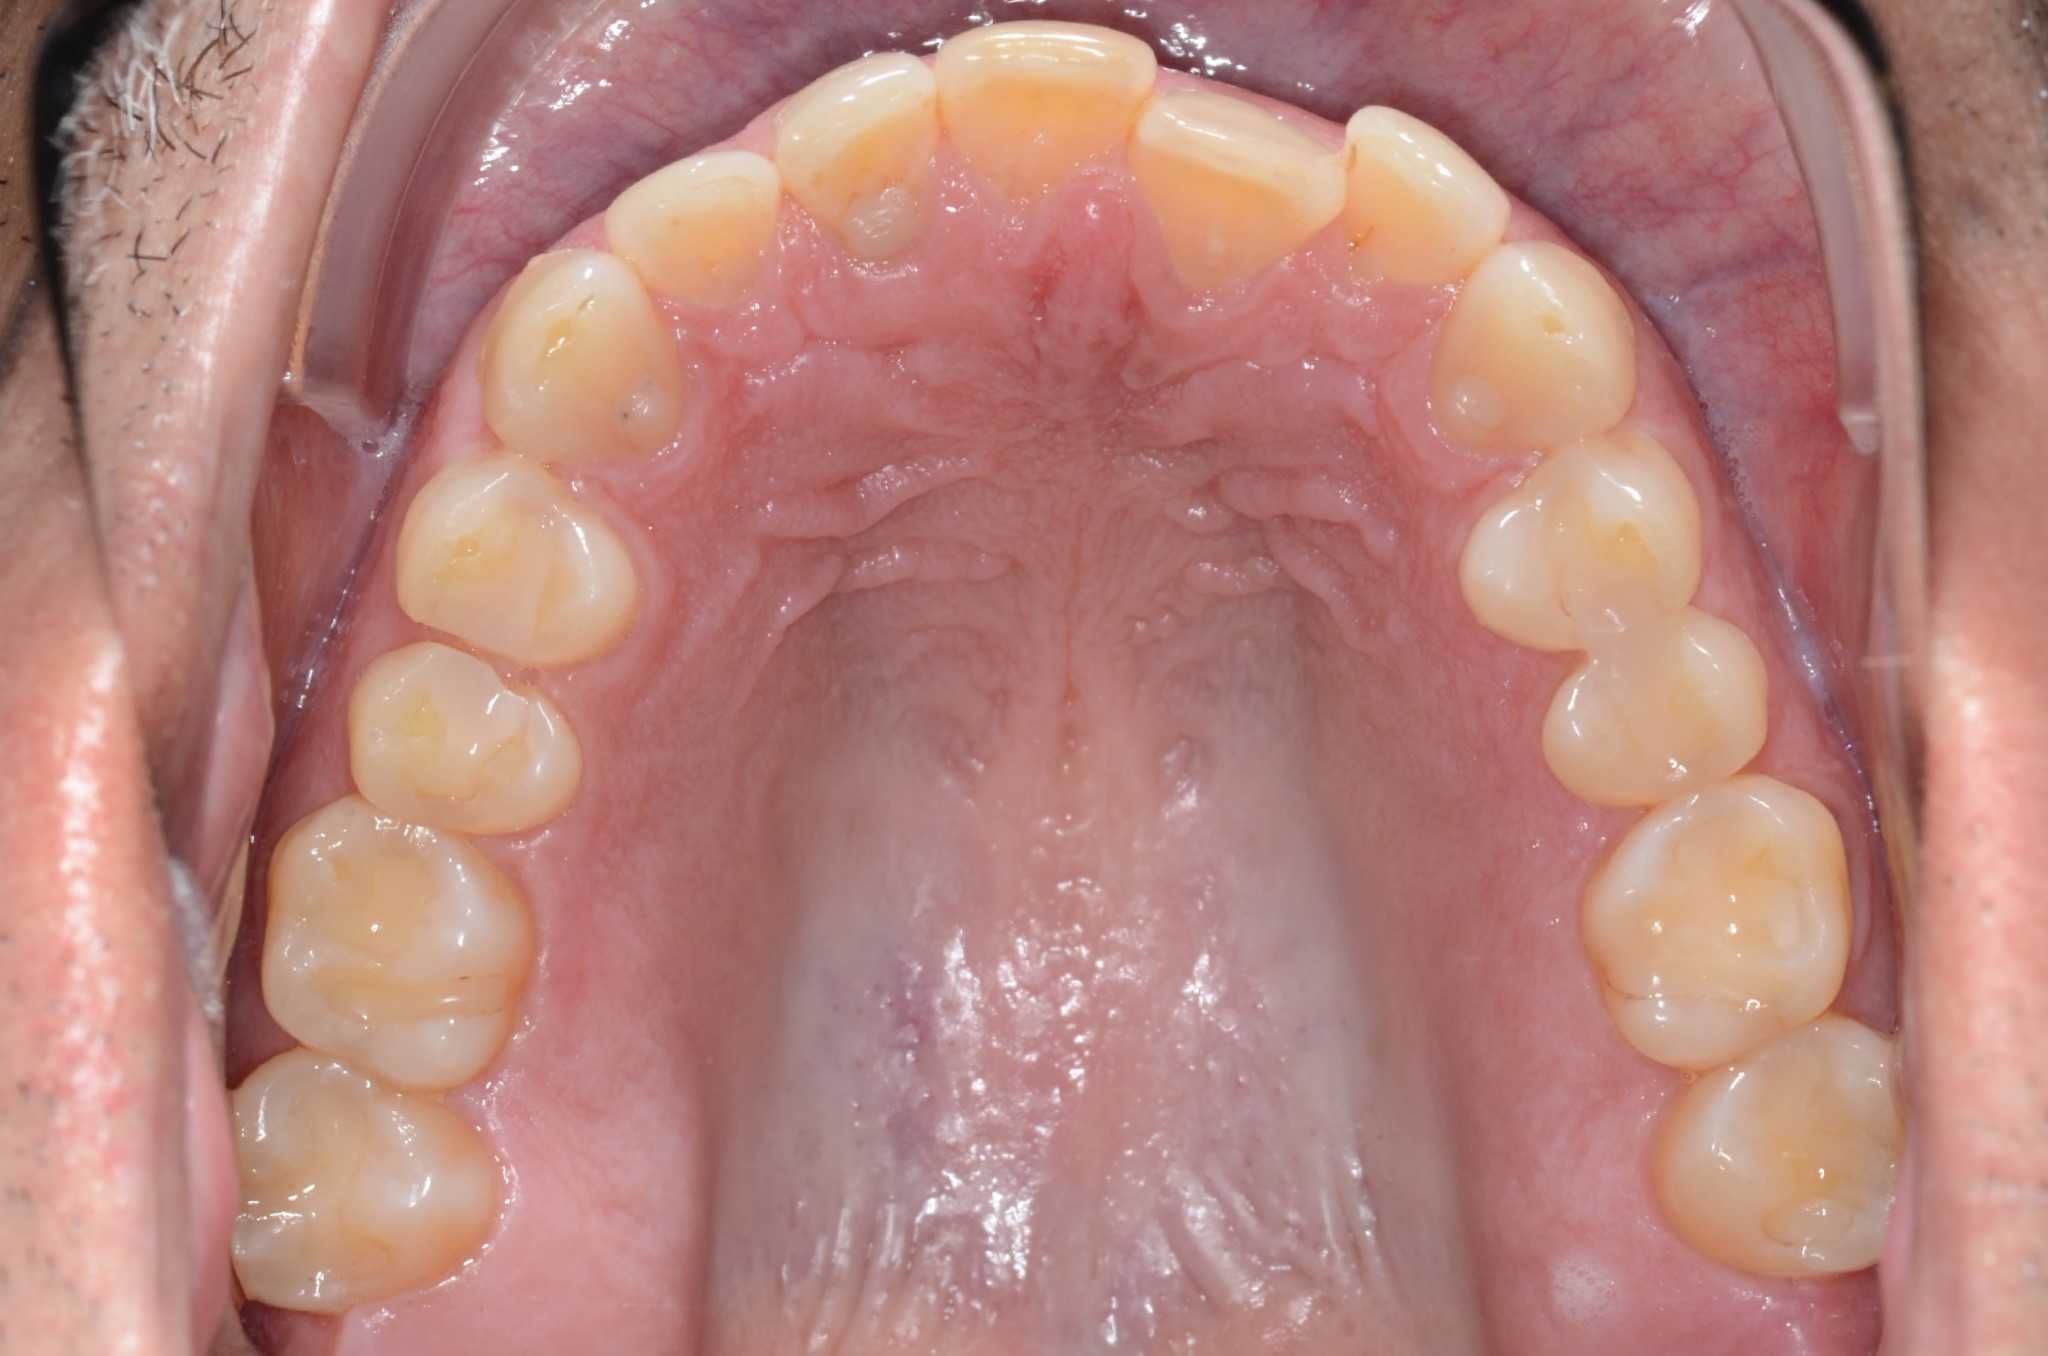

Initial treatment

INTRAORAL